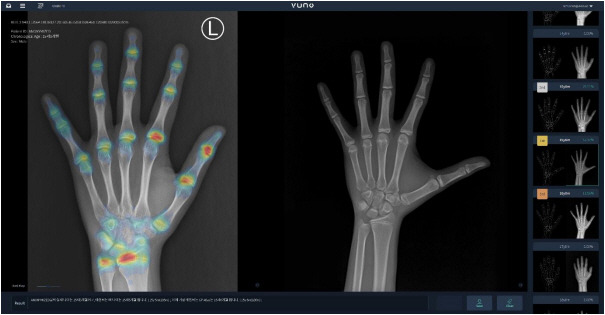

이번 대만 인증을 획득한 뷰노메드 본에이지는 국내 1호 AI 의료기기로, AI를 기반으로 손뼈 엑스레이를 분석해 골연령 판독을 돕는 제품이다. 또 분석 결과를 바탕으로 예측 성장 키 등 성장 정보를 담은 리포트도 제공한다.